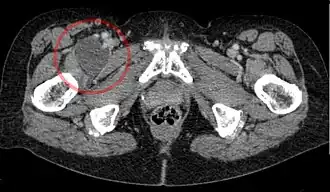

![]() Enlarged iliopectineal bursa in CT - scan | |

The iliopectineal bursa or the iliopsoas bursa is a large synovial bursa that separates the external surface of the hip joint capsule from the tendon of the iliopsoas muscle.[1]

The most proximal of part the iliopectineal bursa lies on the iliopubic eminence of the superior pubic ramus. The iliopectineal bursa passes across the front of the capsule of the hip joint and extends distally downwards almost as far as the lesser trochanter.[2]

The iliopectineal bursa frequently communicates by a circular aperture with the cavity of the hip joint.[1]